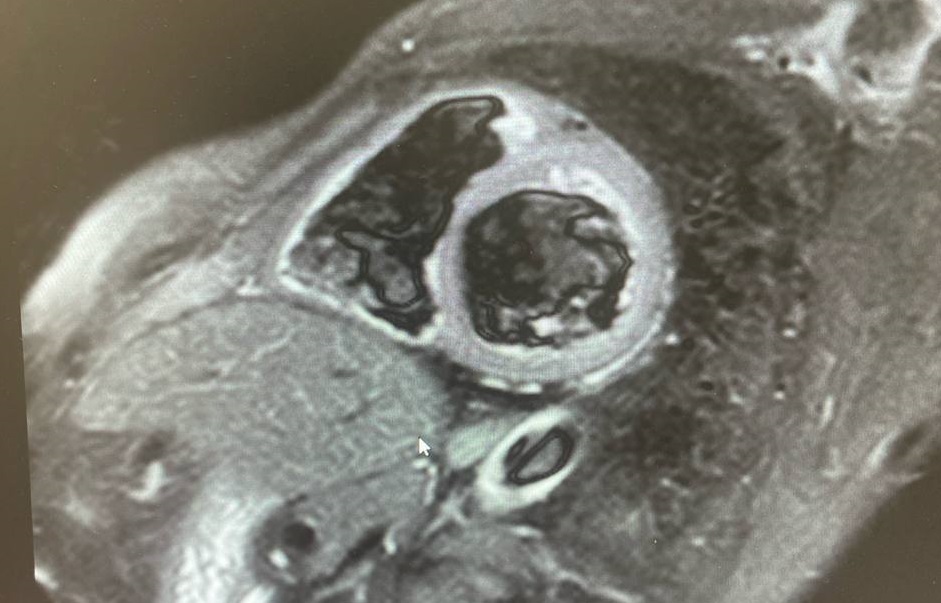

Первым врачом-рентгенологом, прошедшим обучение, стал Фаил Кутлубаев. Позже к направлению присоединилась Анжелика Бузина. Повышение квалификации прошли и рентгенлаборанты — Наталья Бойко и Евгений Зелинский. Сегодня специалисты отдела уверенно диагностируют кардиомиопатии, миокардиты, постинфарктный кардиосклероз и другие сложные патологии сердца.

В планах отделения — дальнейшее развитие диагностических программ, в том числе обучение по патологиям клапанов сердца и выявлению опухолей.